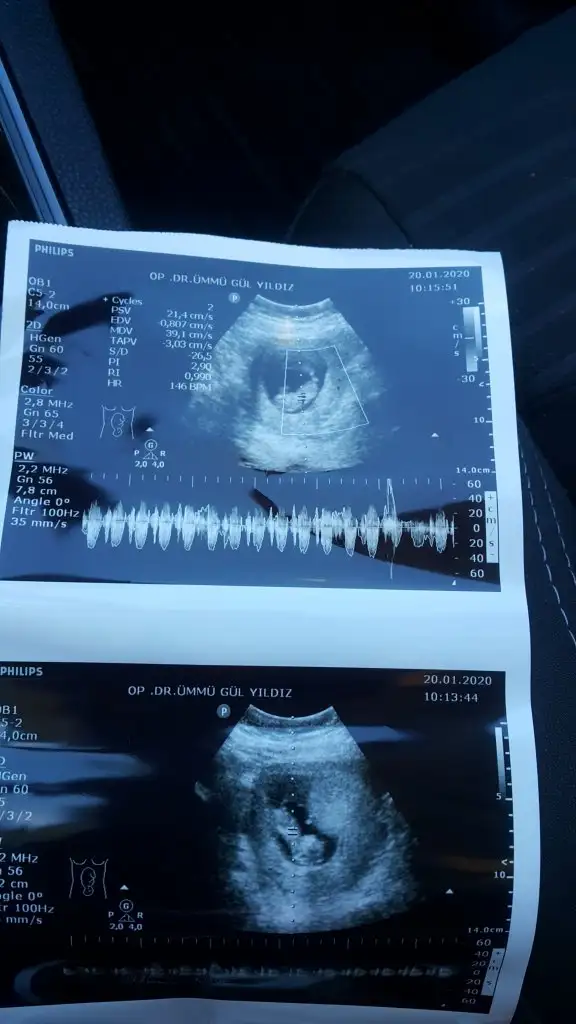

Tahmininiz nedir ?😊

• 20200122_190950.webp

20200122_190950.webp

74,9 KB · Görüntüleme: 73

• 20200122_191032.webp

20200122_191032.webp

67,7 KB · Görüntüleme: 67